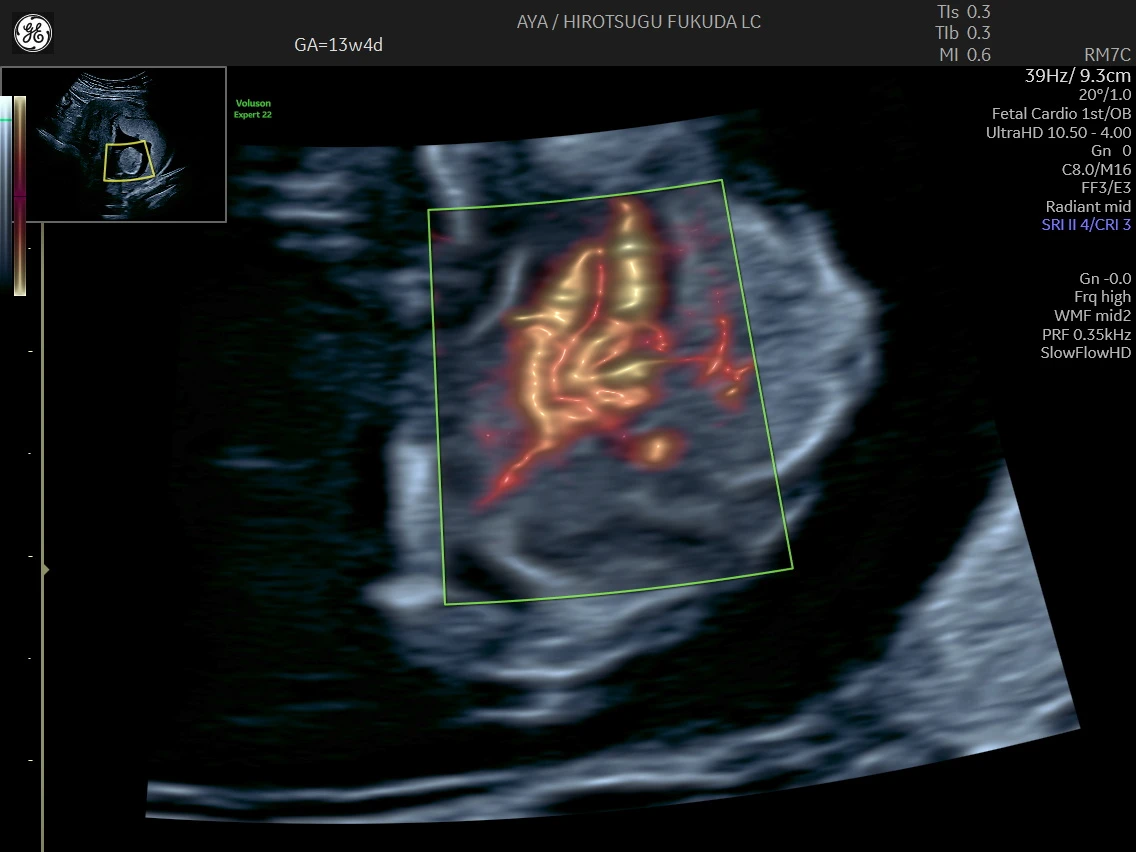

胎児心臓の初期評価

妊娠初期では観察が難しい胎児心臓についても、SlowflowHDを用いた血流描出を併用し、可能な範囲で流出路や大血管の位置関係の評価を行っています。

初期心臓評価の実際

下記は、妊娠初期における血流描出の一例です。初期心臓評価に関する取り組みについては、国際学術誌 Journal of Ultrasound in Medicine にも報告しています。

妊娠13週のslowflowHDによる心臓

妊娠13週の心疾患症例